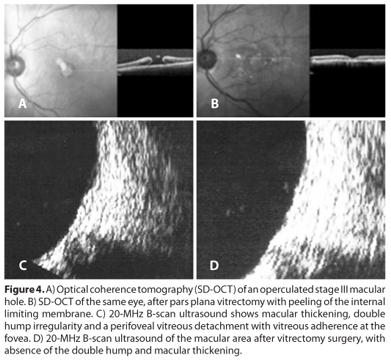

The main value in understanding pathogenic theory is to identify possible therapeutic implications: a vitrectomy with the aim of resolving anteroposterior traction could be the main goal of a surgical procedure when the vitreous face is not totally separated from the edge of the MH. Otherwise, when no anteroposterior traction is shown by OCT or US, the surgeon would attempt to remove epiretinal tissue and internal limiting membrane to release the tangential traction(3). Moreover, the differentiation between VMT and PVD, by a noninvasive technique, is inevitable and decisive for further surgical or pharmacological treatment and the B-scan US served as the most reliable noninvasive technique, between biomicroscopic and OCT, to assess the status of posterior vitreous cortex prior to vitrectomy(18,19) (Figure 4).

Considering MH stage III, the ultrasonographic findings were variable macular thickening, double hump irregularity, with or without images consistent with prefoveal pseudo-operculum (small echodense opacity suspended anterior to the foveolar area) and attached to a thinner echodense linear opacity that appeared to connect to the prepapillary glial tissue nasally, suggesting the diagnosis of a partial PVD.